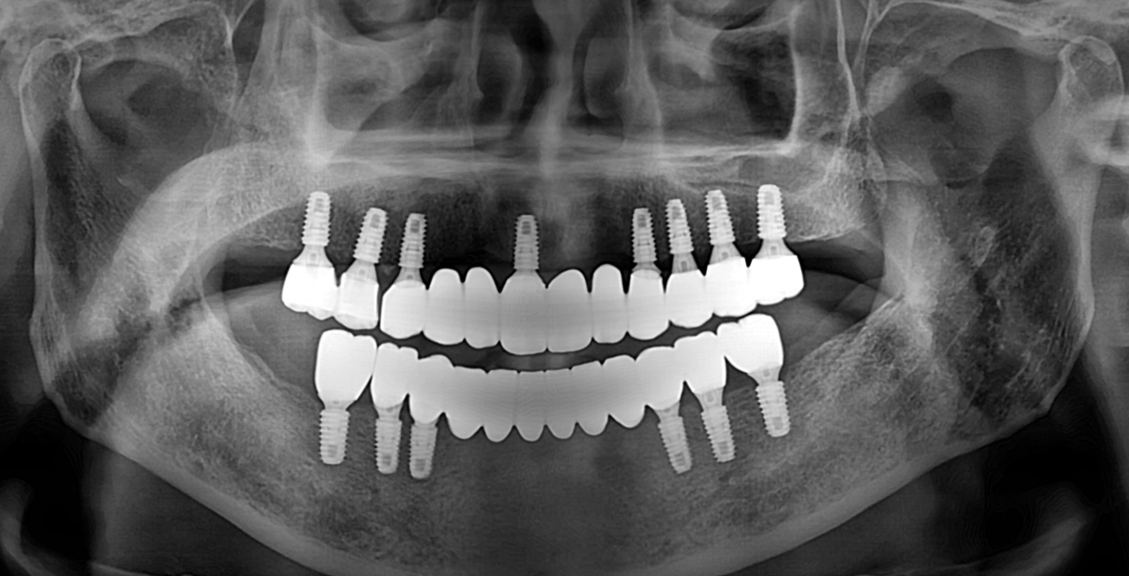

After

임플란트